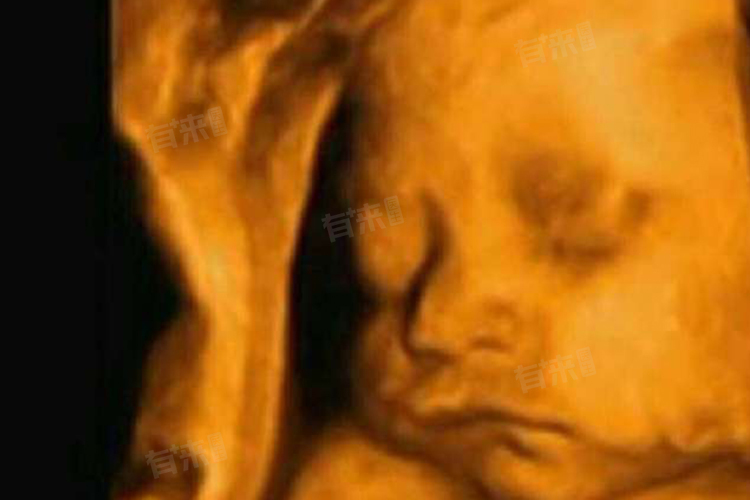

- 胎儿四维彩超是产前检查的重要项目,通过高清晰度成像技术,可立体呈现胎儿的面部及各器官发育情况,对早期发现胎儿先天性体表畸形和先天性心脏疾病等具有重要意义。其最佳检查时间为妊娠20-24周,这一阶段被称为“胎儿大排畸黄金期”。

- 此时胎儿大小适中,肢体舒展,羊水量相对充足,胎儿在子宫内的活动空间较大,超声探头能够更清晰、全面地观察胎儿的头面部、脊柱、四肢、心脏、腹部脏器等结构。同时,胎儿的器官发育已较为完善,大多数严重的结构畸形在此阶段已能显现,便于医生及时诊断和评估,为临床决策提供有力依据。